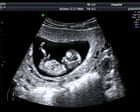

Hospital specialists report cases of missed health problems, misdiagnosed conditions, and women erroneously told their babies had died High street